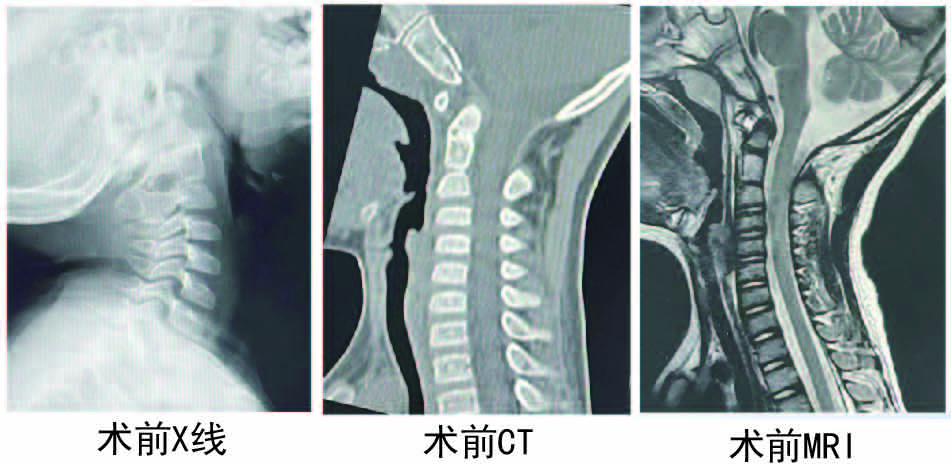

疾病不挑年龄。年仅4岁的男童自出生起便伴有斜颈症状,且随生长发育逐渐加重,已出现头面部严重畸形。由于父母不在身边,孩子由姑姑和爷爷奶奶抚养,清贫的家庭因孩子的疾病更添沉重负担。因患儿年龄过小、病情复杂险峻,家属曾多次带其求医,均遭婉拒。9月8日,李劲松副主任医师接诊后,与家属进行了充分沟通,详细阐释手术风险与预期获益,最终毅然决定承担这一充满责任与挑战的手术。

9月11日,李劲松副主任医师、彭毅主治医师组成的手术团队为患儿实施 “寰枕融合术”。术中,李劲松采用特殊穿刺入路,成功植入常规规格(直径 3.5 毫米,长度 26 毫米)的椎弓根螺钉,确保内固定具备足够矫形强度。手术不仅恢复了患儿的颅颈稳定性,更为其未来颅面正常发育争取了宝贵机会。术后不久,患儿康复出院,斜颈及颈部活动受限症状均明显改善。